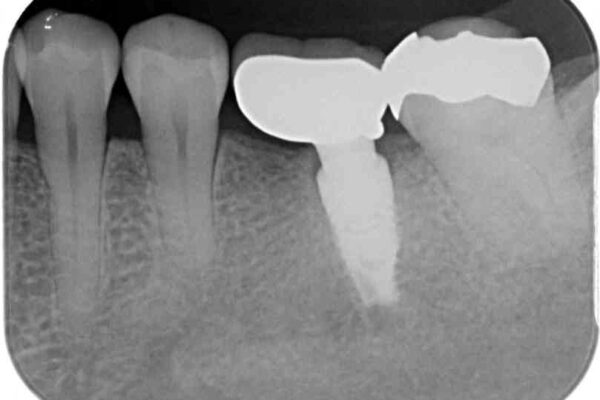

銀歯の装着されている奥歯がしみるとのことで来院された患者様です。

銀歯周辺の歯が欠けており、むし歯も進行している状態であったので、オールセラミッククラウンにて補綴治療を行うこととしました。

• しみる奥歯 オールセラミッククラウンによる補綴治療 治療前画像